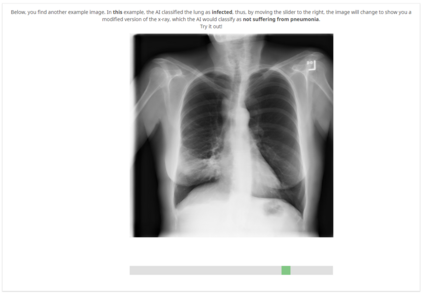

With the ongoing rise of machine learning, the need for methods for explaining decisions made by artificial intelligence systems is becoming a more and more important topic. Especially for image classification tasks, many state-of-the-art tools to explain such classifiers rely on visual highlighting of important areas of the input data. Contrary, counterfactual explanation systems try to enable a counterfactual reasoning by modifying the input image in a way such that the classifier would have made a different prediction. By doing so, the users of counterfactual explanation systems are equipped with a completely different kind of explanatory information. However, methods for generating realistic counterfactual explanations for image classifiers are still rare. Especially in medical contexts, where relevant information often consists of textural and structural information, high-quality counterfactual images have the potential to give meaningful insights into decision processes. In this work, we present GANterfactual, an approach to generate such counterfactual image explanations based on adversarial image-to-image translation techniques. Additionally, we conduct a user study to evaluate our approach in an exemplary medical use case. Our results show that, in the chosen medical use-case, counterfactual explanations lead to significantly better results regarding mental models, explanation satisfaction, trust, emotions, and self-efficacy than two state-of-the-art systems that work with saliency maps, namely LIME and LRP.